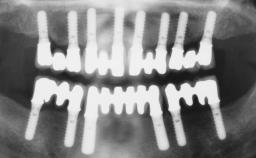

Immediate Loading of Six Implants in the Mandible and Six Implants in the Maxilla and Final Restoration with Full-Arch CAD/CAM Metal Framework FDPs Involving Digital Planning and Guided Surgery

# of Implants 12

Type of Implants One-Piece

Guided Surgery Yes

Abutment Type CAD/CAM

Prosthesis Type FDP